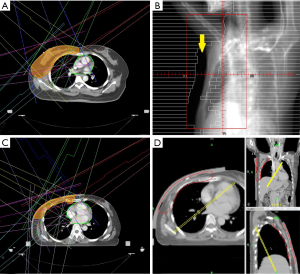

In WBRT group, an IMRT plan consisted of 2 to 7 IMRT field directions, depending on individual patient’s anatomy and PTV distribution shape (Figure 1A). In addition, “skin flash”, a field extension of 20 mm outside the skin surface, was used to deliver additional radiation on the space above the skin to cover the intra-fractional movement caused by respiration (Figure 1B). In HT plans for WBRT, a directional block at contralateral posterior thorax was designed to reduce the radiation from posterior and contralateral direction and reduce dose of lung and heart. Virtual bolus, which was a pretended material on the breast surface in treatment planning but absent during irradiation, was used in all the HT plans for WBRT to cover the patient’s movement. The density of virtual bolus in this study was defined as 1.0 g/cm3, and thickness was 10 mm.

In PMRT group, an IMRT plan consisting of 7 IMRT field directions was designed with 20 mm skin flash (Figure 1C). A 5-mm tissue equivalent bolus was added on patient’s ipsilateral chest wall to ensure the superficial coverage. On the other hand, 10 mm tissue equivalent bolus was added for patient in PMRT group treated with HT. A directional block was also used to restrict the beam angle (Figure 1D).